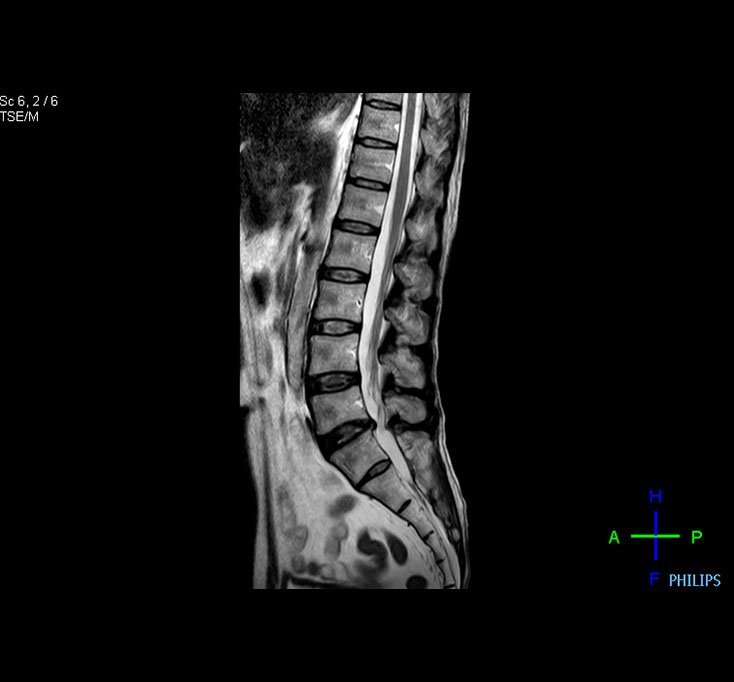

Lumbar Spine MRI

Best magnet homogeneity in the industry ( Most important in orthopedic imaging and body imaging )